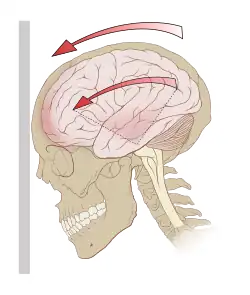

Ukázka otřesu mozku | |

Na mozek působí přímo či nepřímo mechanická síla, která je patogenním faktorem. Přímé působení při nárazu se nazývá "coup", nepřímé pak "countercoup" (např. při dopadu výsadkáře na paty a otřesu těla).